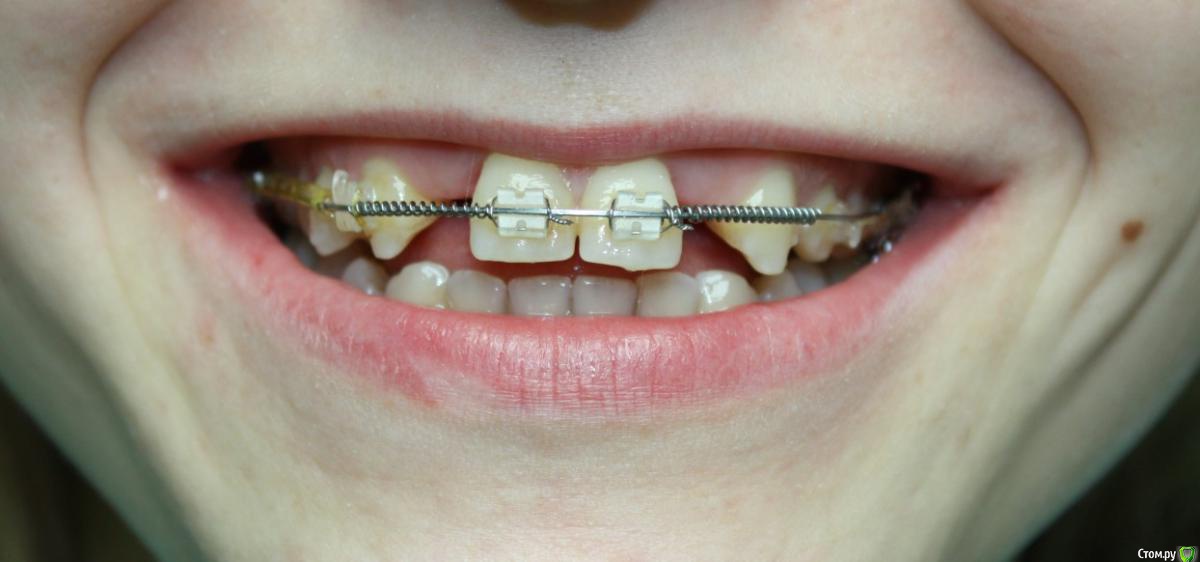

Здравствуйте коллеги! На консультацию обратилась пациентка, сейчас находится на ортодонтическом лечении. Предистория: три года назад обратилась к стоматологам с жалобой на неудовлетворительную эстетику фронтального отдела, вследствие врожденного отсутствия латеральных резцов. Ей было предложено ортодонтически создать место для боковых резцов, затем провести имплантацию и протезирование на имплантатах 12, 22.

Затем, с ее слов, идет длительный этап ортодонтии, почти 3 года, вследствие которого получили немного места для двоек, которого не достаточно для иплантации, так же центральные резцы ушли вперед, образовалась саггитальная щель.

Ортодонт предлагает удалять восьмерки, ставить брекеты Дэймон на вч и нч, мини винты в ретро молярную область  и продолжать ортодонтическое лечение, создавать место для двоек. Пациентка пока пошла делать новое КТ,

Фото сегодня:post-461-0-94195200-1456407270_thumb.jpgpost-461-0-97652100-1456407271_thumb.jpgpost-461-0-40898500-1456407273_thumb.jpgpost-461-0-68973300-1456407274_thumb.jpgpost-461-0-88108800-1456407275_thumb.jpgpost-461-0-99061300-1456407276_thumb.jpgpost-461-0-92547500-1456407277_thumb.jpgpost-461-0-02811200-1456407279_thumb.jpgpost-461-0-05035300-1456407280_thumb.jpgpost-461-0-27197600-1456407281_thumb.jpg